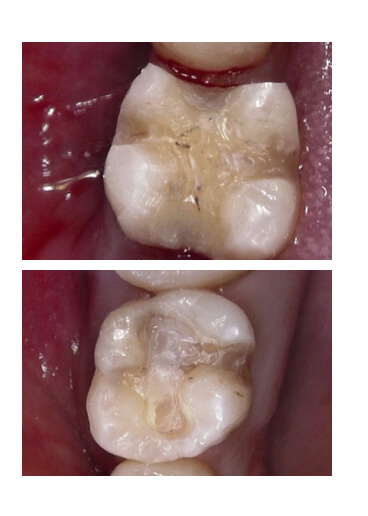

②虫歯部分を染色

小さく見えても、中で大きく広がっていることもあります。

④一見、虫歯がないように見えますが…

⑤詰め物を外すと、虫歯になっていることもあります(二次虫歯)

内面が黒ずんでいるのは、カビや銀歯の錆びが、飲み込まれずに溜まっているからです。